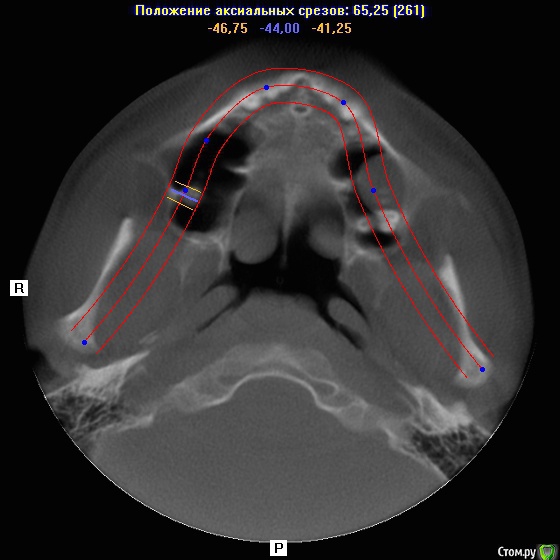

Добрый день коллеги,плановое удаление 8 зубов ,верхние в гайморовой ,что за образование в левой жалоб нет никаких.Что вы делаете при вскрытии пазухи?